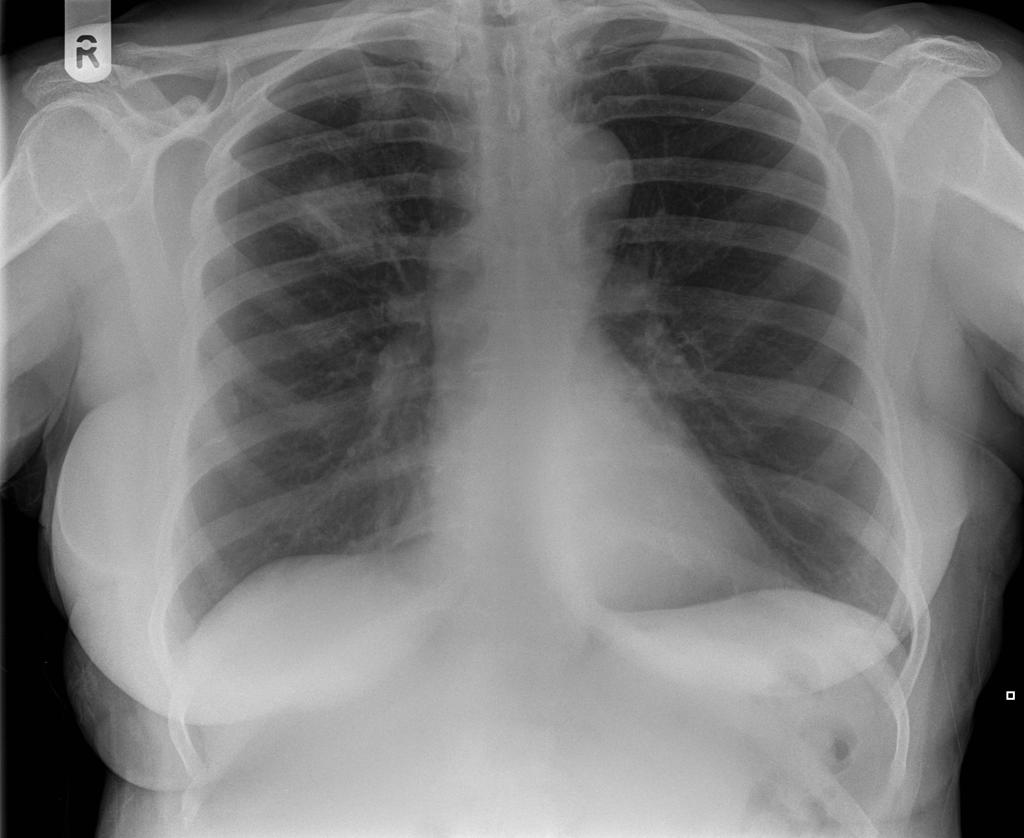

Du undersøger Tove:

Saturation: 94%, auskultation: Ronchi og crepitationer over højre underlap. Temp 39. CRP 120.

Du stiller diagnosen bakteriel pneumoni.

Du vil gerne give Tove penicillin V, men hun har CAVE.

Hvad giver du Tove?

Doxycyclin

Da du skal til at udskrive Doxycyclin, ser du at patienten får LABA og ICS...

Hvilket præparat tillægger du udover Doxycyclinen?

tbl. Prednisolon